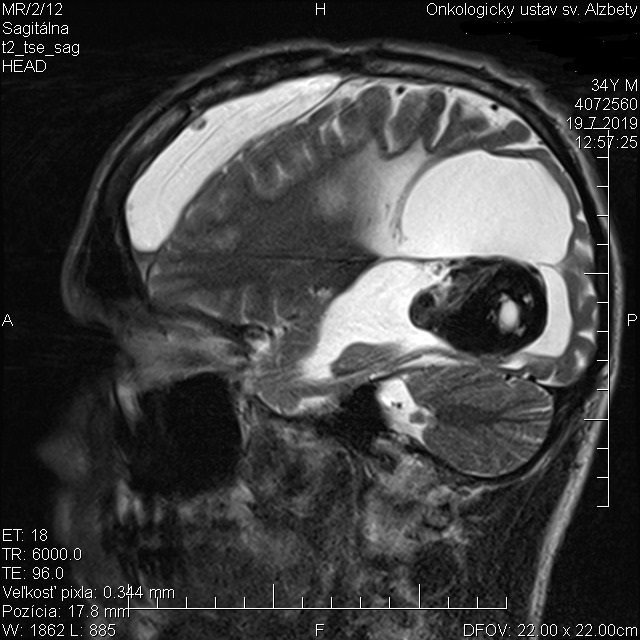

@janina9410 Nemusis hovorit nic. Ved vidis, ze je to vsade okolo nas. Zijeme v jednom nedokonalom svete. Je to nieco strasne, ja sa uz nemozem pozerat na to utrpenie. Keby som mohol, tak by som vsetkych vyliecil. Vzdy hovorim, ze zdravie by malo byt pre vsetkych rovnake, vsetko ostatne uz je na nas. ci je uz niekto milionar alebo bezdomovec. Co sa tyka lekarov, tak z teba mam pocit, ze ty sa ich nebojis a chapes, ze su to obycajni ludia. Ja mam s nimi tolko skusenosti, ze by som mohol napisat knihu. Od oktobra som zaval odpadavat a uz 2x ma v bezvedomi viezla RZP z ulice. Bol som teda za onkológom, ze asi sa nieco deje, tak by mi mali urobit MRI skor a necakat az do jula, kedy mam termin. On mi povedal, ze kym nezvraciam a nevidim dvojmo, tak netreba. Ja som vlastne kontaktoval vsetky popredne kliniky na SK aj v CZ, no vsade mi povedali, ze im je luto, no uz mi nevedia pomoct. Aj ked jedni argumentovali mnozstvom nadorov, druhi zasa pooperacnou dierou, ktora sa po operacii vytvorila a zaliala mozgovym mokom. Vraj, keby to otvorili, tak tekutina by sa vyliala, diera by sa zosypala a mna by to zabilo. Takto to vyzera z boku. Ten nador je zostatok z operacie a biely flak na cele je hematom, ktory sa tiez zvacsuje.